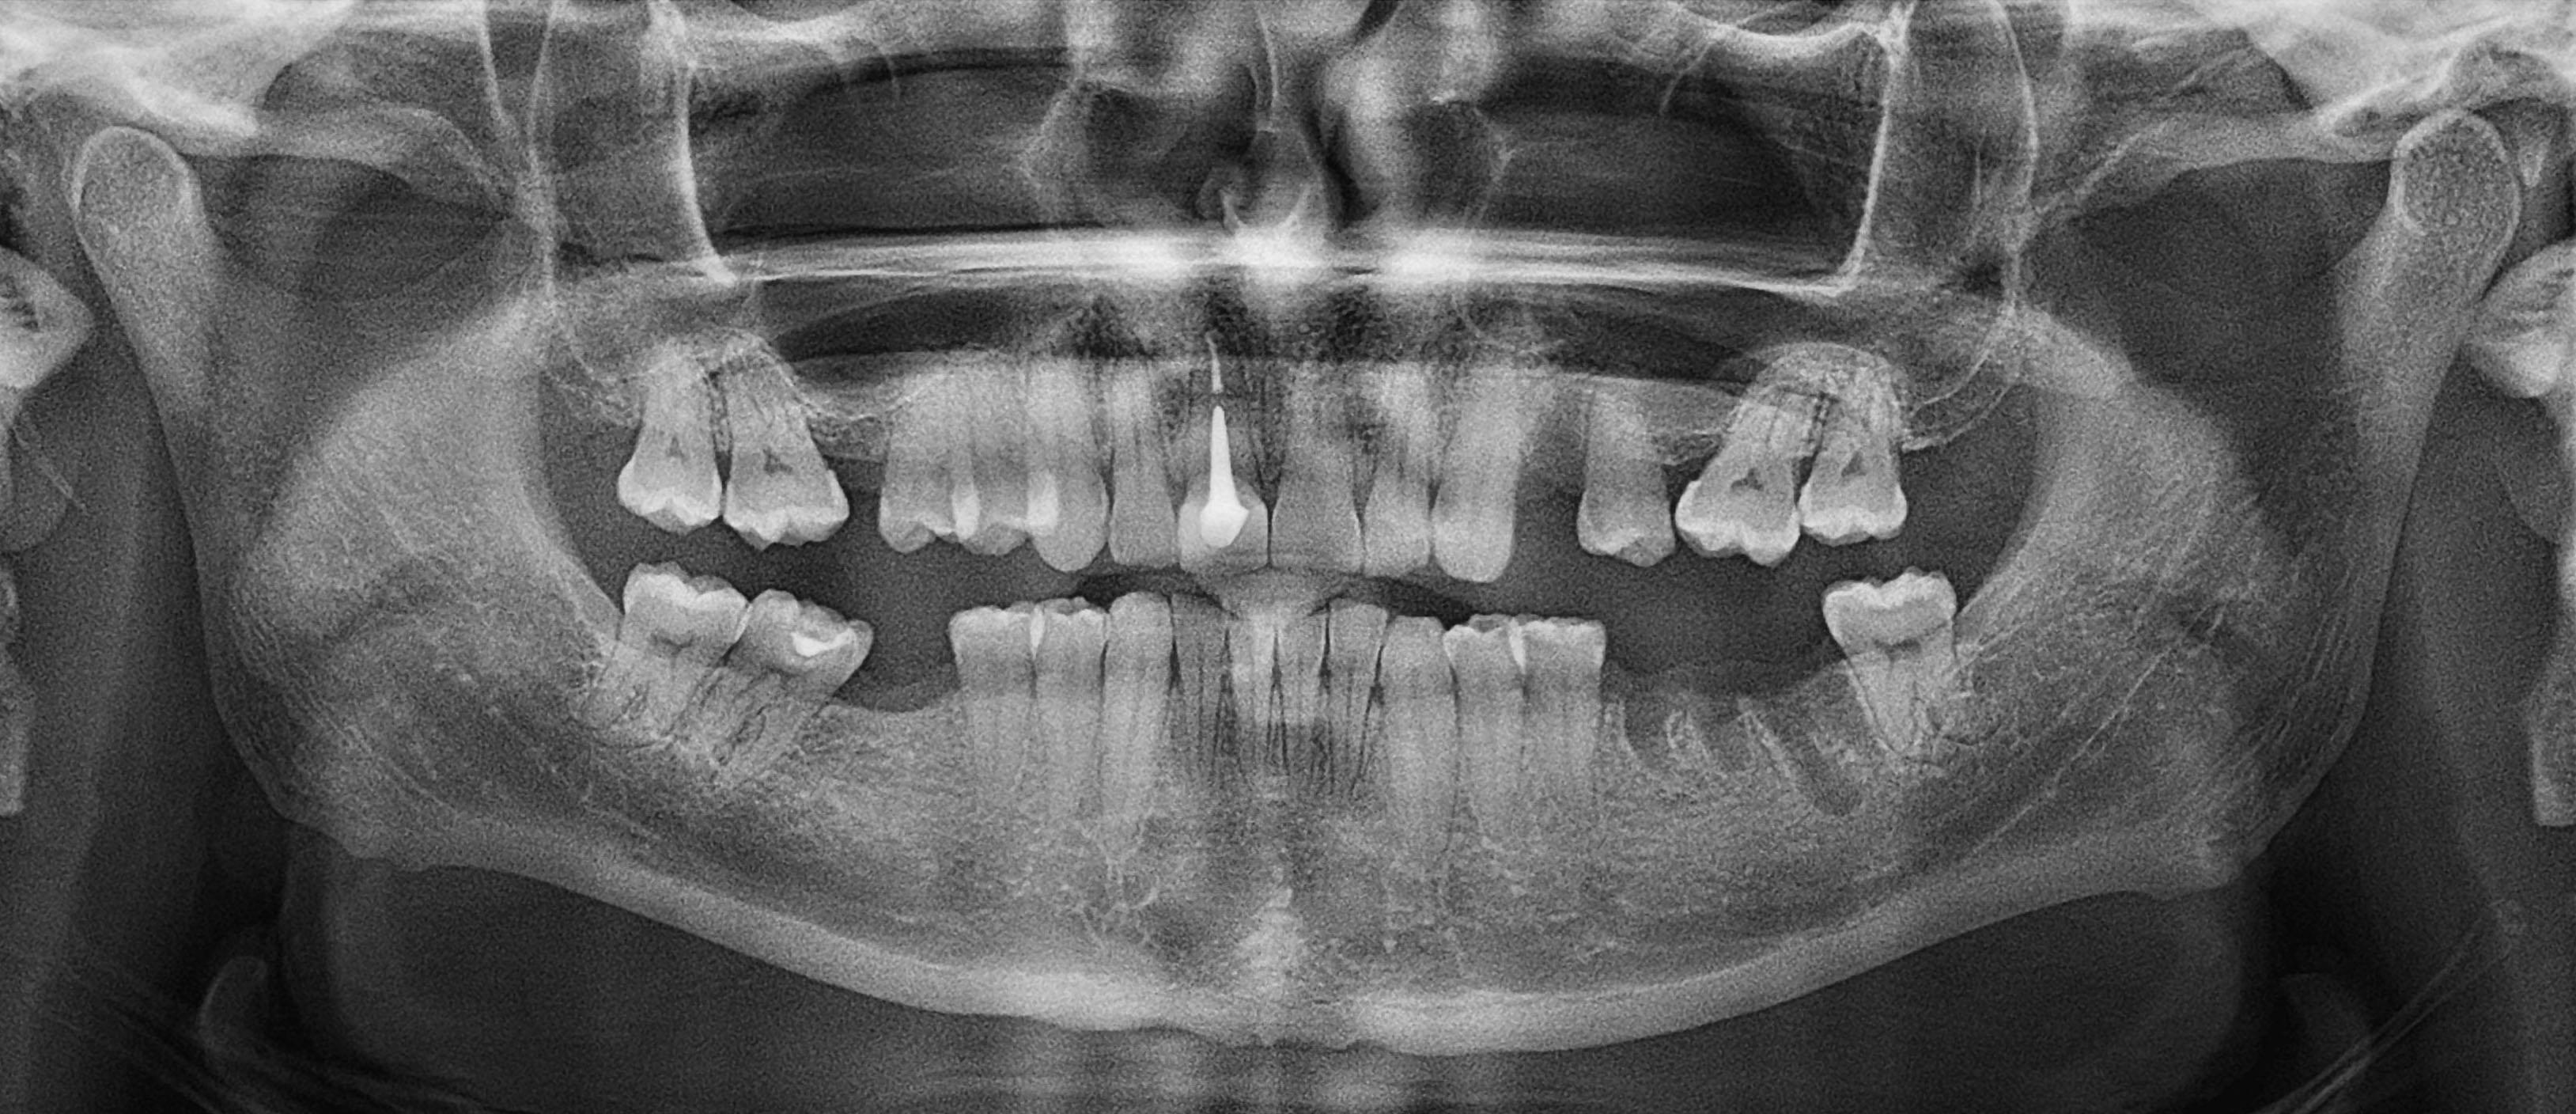

Panoramatický snímek (OPG)

Typ vyšetření - 2D

Cena - 450 CZK

Celková doba přijetí je 15 minut

Čas skenování - 10 s

Tisk na fotografický papír / e-mail / lékař na Cloud